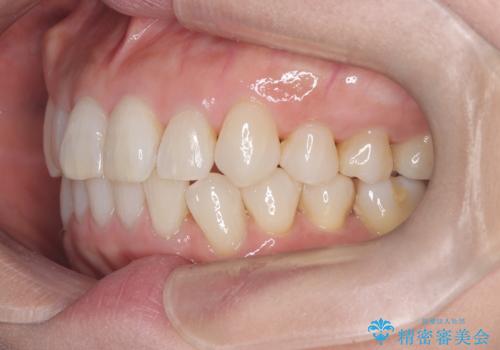

インビザラインで非抜歯矯正|ゴムかけで下顎犬歯の低位を改善し、噛み合わせも最適化

- 患者様は、下顎の犬歯が通常より低い位置にあり、噛み合わせのバランスが崩れていることを気にされて来院されました。診査の結果、抜歯せずに歯をきれいに並べるスペースを確保しながら、**ゴムかけ(顎間ゴム)**を使用して下顎犬歯の高さを適正に調整する方針を立てました。併せて、奥歯の噛み合わせも改善し、全体のバランスを整えることを目標としました。

治療はインビザライン(マウスピース矯正)を使用し、歯列全体を計画的に移動させながら、下顎犬歯の低位をゴムかけによって徐々に引き上げました。患者様にはゴムの装着をしっかり継続していただき、順調に改善が進行。最終的に奥歯の噛み合わせも安定し、全体の咬合バランスが整いました。治療後は「自然な噛み心地になり、見た目も満足」と患者様にも喜んでいただきました。